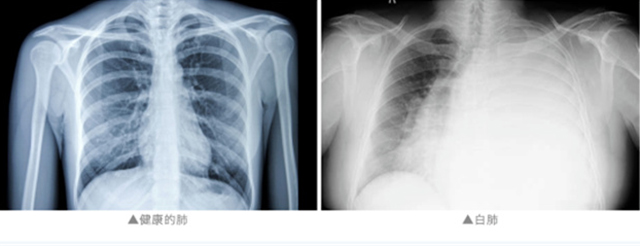

医生介绍 陈女士因基础病免疫力偏低 得了流感后硬扛 大大增加了致病真菌的感染风险 最终导致白肺 通常来说 “白肺”是指急性呼吸窘迫综合征 主要发生在重症感染时 双肺弥漫性病变进展迅速 其症状和严重程度 都与支原体肺炎不同